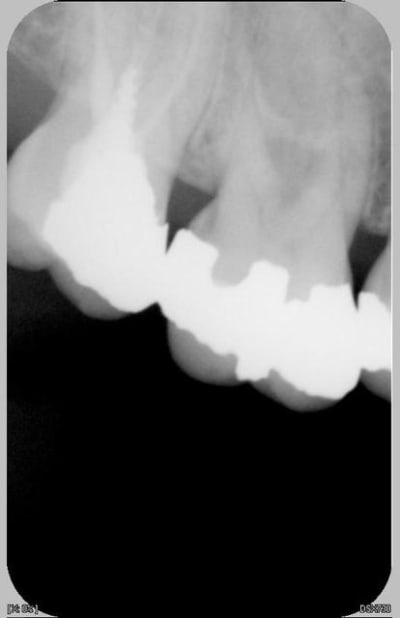

La série. Trois urgences différentes avec a priori un problème similaire.

Dans les trois cas , nuit difficile

Douleur à la pression localisée sur un dent particulièrement. Pas douleur au froid. Douleur au chaud et évidemment à la percussion.

Pas de gingivite autour de la dent si ce n'est ponctuellement en vestibulaire. La sonde pénétre nettement en interradiculaire unique siège de la douleur pour les 3 dents et uniquement en interradiculaire pour la radio 1 et 3.

Les radios 1, 2 et 3 sont ici